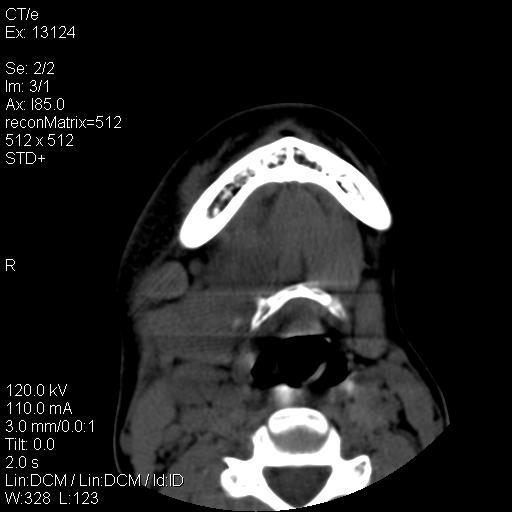

标题: CT18257:女,29岁,右下磨牙痛 [打印本页]

标题: CT18257:女,29岁,右下磨牙痛

女,29岁,右下磨牙痛,因产后2月,故未治疗。现右颌肿痛伴张口困难。请大家看看右侧鼻咽部、口咽部是否

1.考虑右侧下颌区脓肿(牙源性)

考虑右下智齿冠周炎伴周围软组织炎症,脓肿形成

1)考虑右侧下颌区软组织脓肿(牙源性)。2)鼻咽部炎性改变;建议追踪复查。3)右侧上颌窦炎。4)双侧下鼻甲黏膜肥厚。